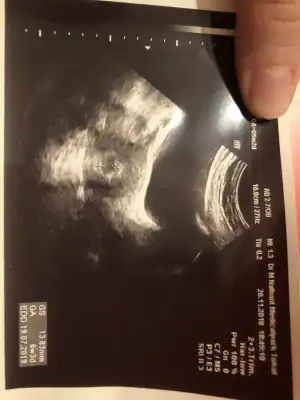

Evet ya da tatilde bir bebek bulduk deriz

Sormayın biz de istedik denedik Allah nasip etti oldu.. ilk bebek 4 aylıkken hamile kaldım yani aralarında 13 ay var.. Simdi 2. ve 3. arasında da 28 ay olacak nasipse. Yani doğumdan sonra çocuklarım 3.5, nerdeyse 2.5 ve yenidoğan olacak kısmetse.